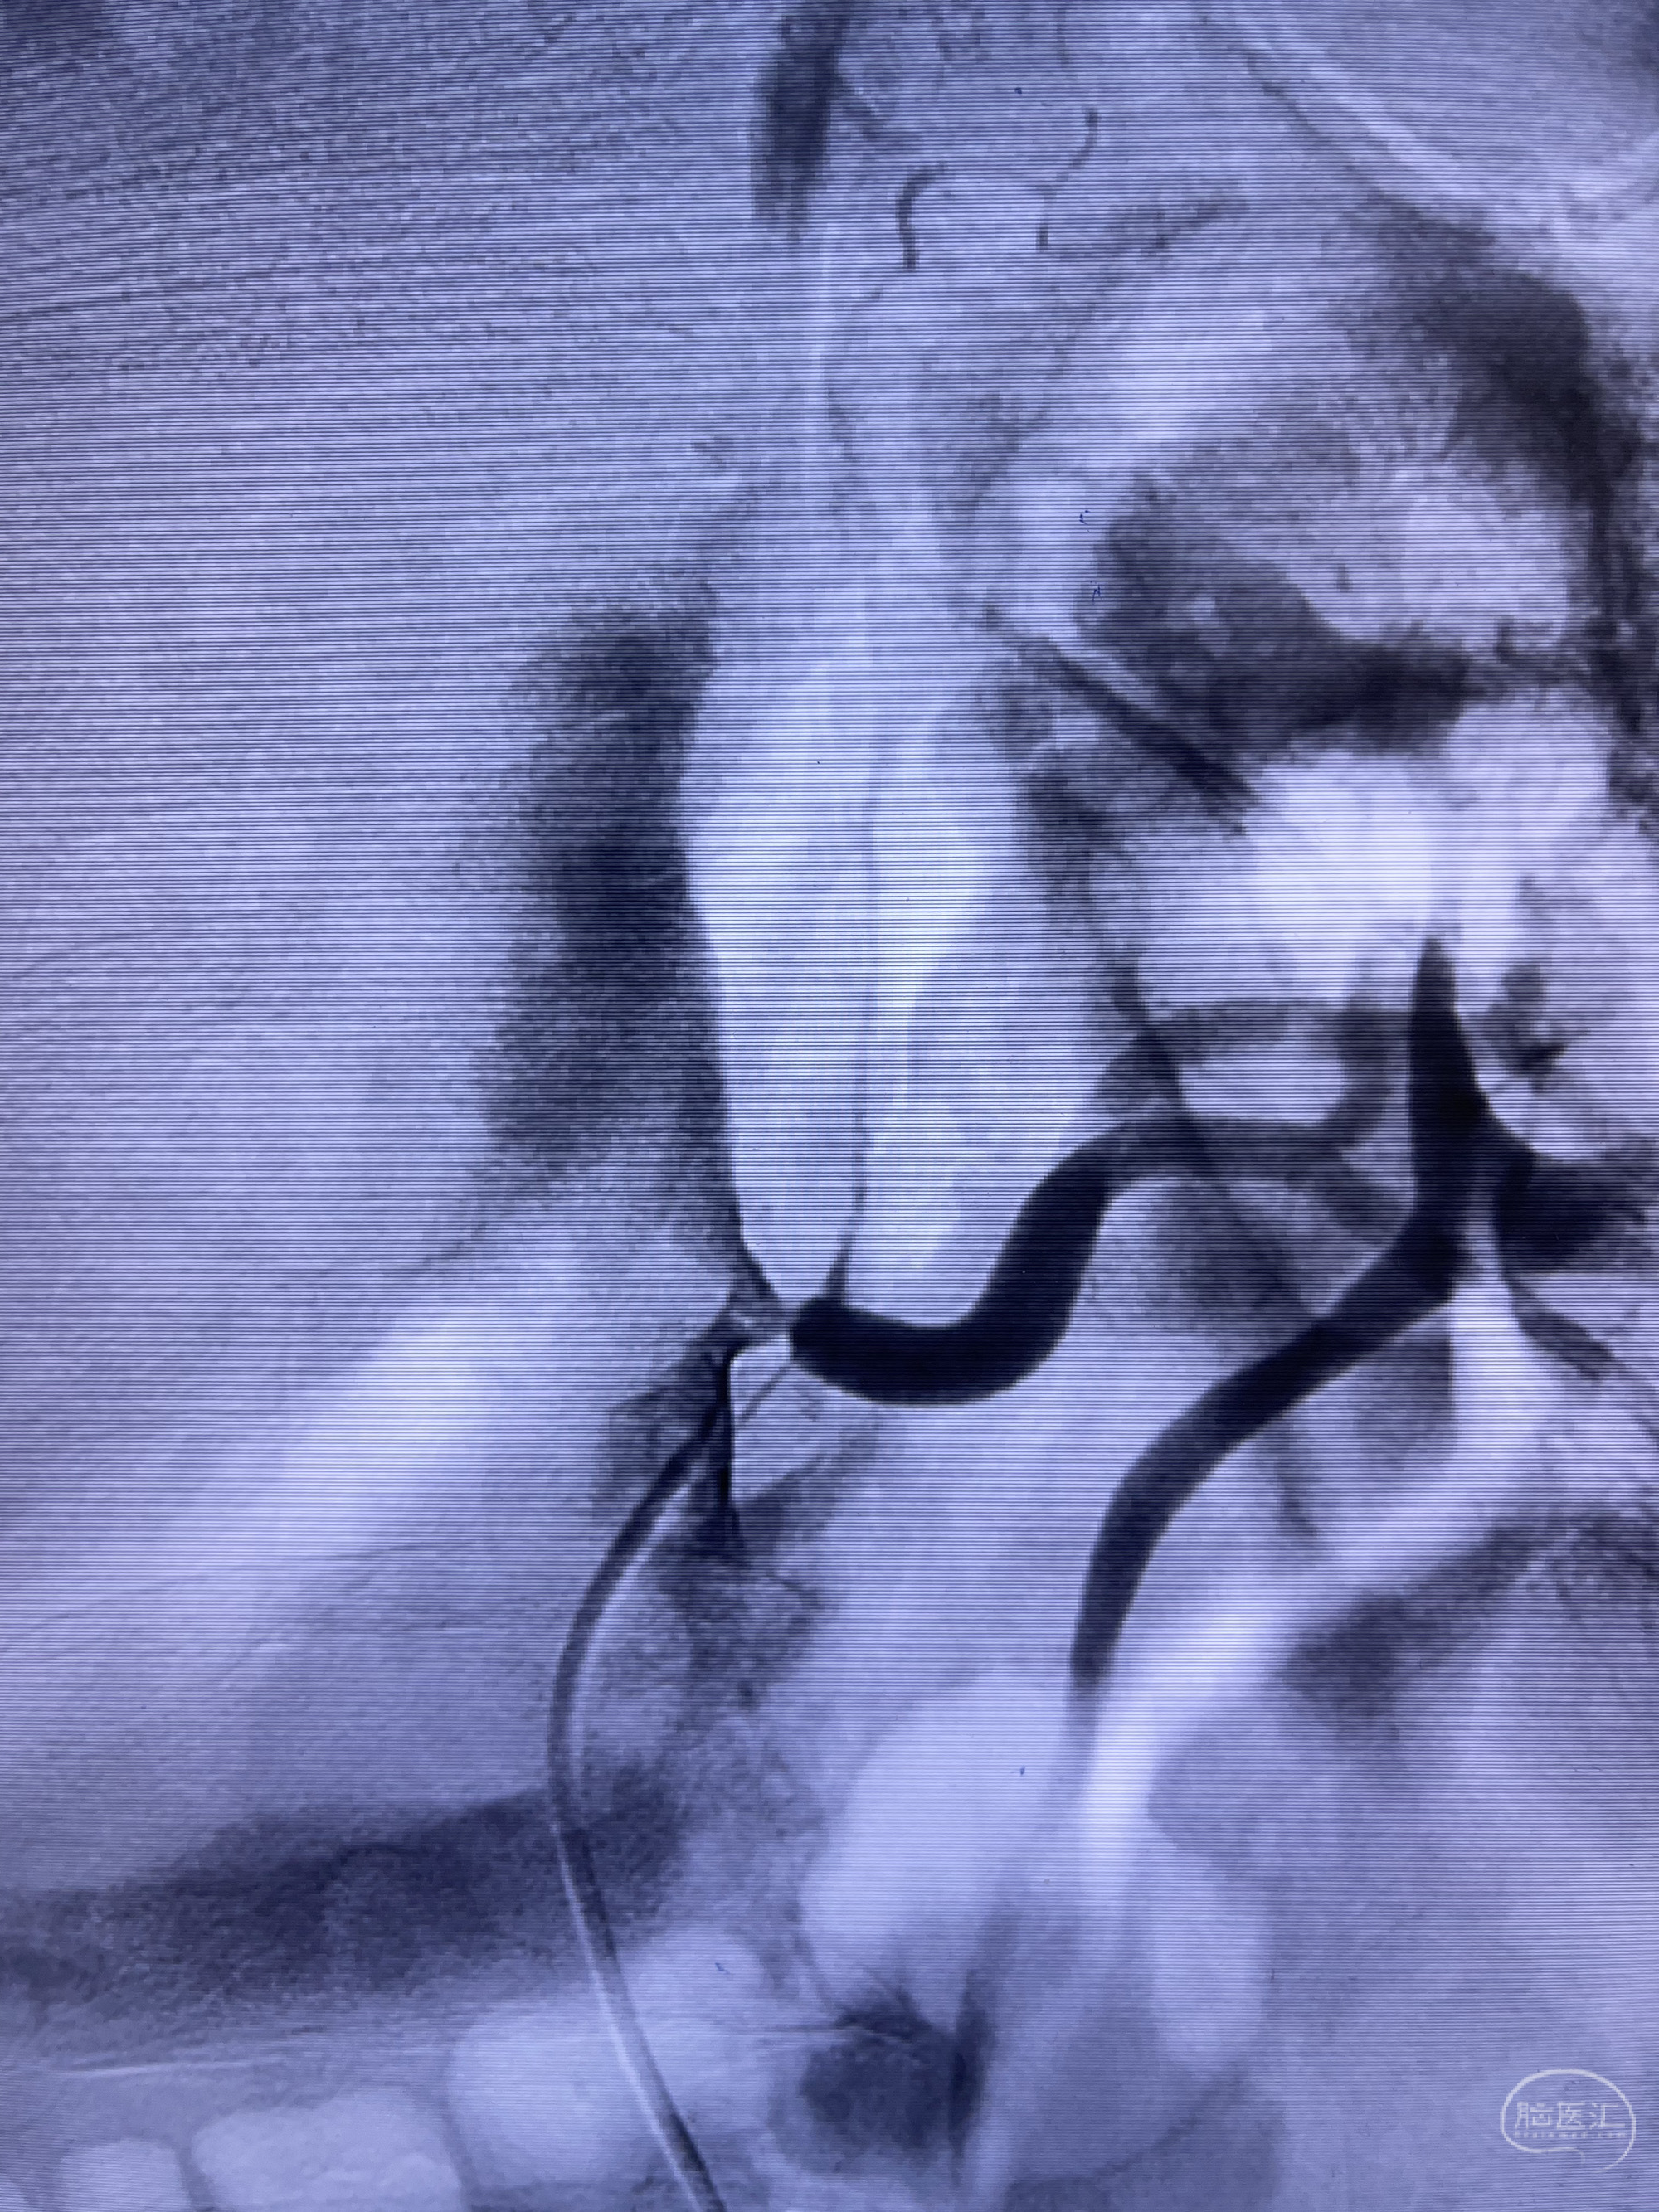

脑血管造影2023.03.06:右侧颈内动脉颈段至岩骨段闭塞,可见后后循环通过原始三叉动脉吻合代偿至海绵窦段,后交通区可见囊状造影剂填充影,左侧锁骨下动脉呈“残端”改变,呈“右侧颈总动脉支架成形术后改变”,支架内血流通畅,可见后交通吻合显影至左侧大脑后动脉,并可见左枕动脉吻合椎动脉至锁骨下动脉

2.右侧颈内动脉由后循环经右侧后交通动脉前向代偿显示

3.右侧颈内动脉眼动脉段近后交通动脉处重度狭窄伴前壁不规则动脉瘤

4.右侧颈外动脉可见经由右侧脑膜中动脉吻合显影右侧眼动脉及颈内动脉

1.箭头处为右侧颈内动脉后交通动脉处重度狭窄,狭窄前壁为不规则动脉瘤;

2.狭窄远端颈内动脉由左侧颈内动脉经左侧后交通动脉—基底动脉顶—右侧后交通—右侧颈内动脉—右侧大脑中动脉途径代偿

左侧颈内动脉经左侧后交通动脉—基底动脉顶—右侧后交通—右侧颈内动脉—右侧大脑中动脉途径代偿